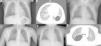

El primer paciente es un niño de 13 meses que acude a urgencias por un síndrome febril y cuadro respiratorio de 48h de evolución. En la radiografía de tórax se aprecia una lesión quística solitaria en el lóbulo inferior izquierdo (fig. 1A). Se completa el estudio con TC torácica (fig. 1B) en la que se confirma la presencia de una cavidad aérea de paredes finas situada en el lóbulo inferior izquierdo, que mide 2,9×3×3,1cm. Como antecedentes personales nuestro paciente había presentado con 6 meses una neumonía en otra localización, sin apreciarse en ese momento lesiones quísticas en la radiografía de tórax (fig. 1C). La familia refiere además que con 12 meses de edad había presentado otro episodio febril con cuadro respiratorio asociado que no cedió hasta recibir tratamiento antibiótico, pero no se realizó radiografía de tórax en dicho episodio.

A) Radiografía de tórax PA: quiste aéreo unilocular en la base pulmonar izquierda. B) TC torácica: cavidad aérea de paredes finas en el lóbulo inferior izquierdo. C) Radiografía de tórax PA: aumento de densidad en lóbulo pulmonar superior derecho. No se aprecia ninguna lesión quística. D) Radiografía de tórax PA: quiste aéreo unilocular en el pulmón derecho. E) Radiografía de tórax PA: aumento de densidad en el pulmón derecho. F) TC torácica: imagen quística unilocular con contenido aéreo y pared fina, localizada en el segmento apical del lóbulo inferior derecho.

Nuestro segundo paciente es un niño de 3 años en el que se descubre de forma casual una lesión quística solitaria en hemitórax derecho en una radiografía de tórax (fig. 1D). El paciente está completamente asintomático desde el punto de vista respiratorio. Como único antecedente a destacar, a los 11 meses había presentado un episodio de neumonía en esa misma localización (fig. 1E). No se realizó ninguna radiografía de control después de ese episodio, ni tampoco existen radiografías previas. Se solicita una TC torácica (fig. 1F) para completar estudio que confirma la presencia de una imagen quística unilocular con contenido aéreo y pared fina, localizada en el segmento apical del lóbulo inferior derecho, con dimensiones de 4×3,5×4,5cm, sin otras lesiones asociadas.